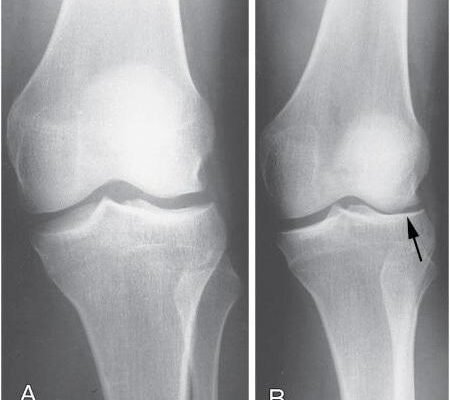

Діагностика хвороби Шляттера зазвичай не становить труднощів. Здоров’я коліна вивчається через фізичний огляд, включаючи пальпацію та рухи, які можуть викликати біль. Для уточнення можуть застосовувати рентген або ультразвукове дослідження, щоб виключити інші захворювання.